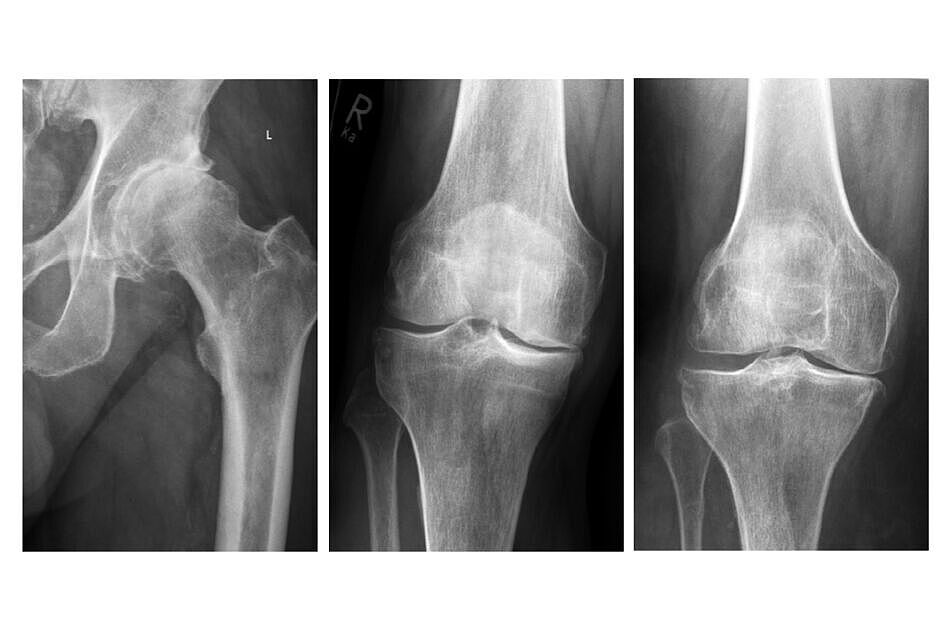

Die Arthrose (Gelenkverschleiß) von Hüft- und Kniegelenk kann ohne vorheriges Unfallereignis (primäre Arthrose) oder als Folge einer Verletzung oder eines Bruches (sekundäre bzw. posttraumatische Arthrose) entstehen. Die Arthrose des Hüftgelenkes ist sogar unter bestimmten Bedingungen durch die gesetzliche Unfallversicherung als Berufskrankheit anerkannt.

Quelle: BG Klinik Tübingen – Röntgenbilder einer Arthrose des Hüftgelenkes

und des Kniegelenkes